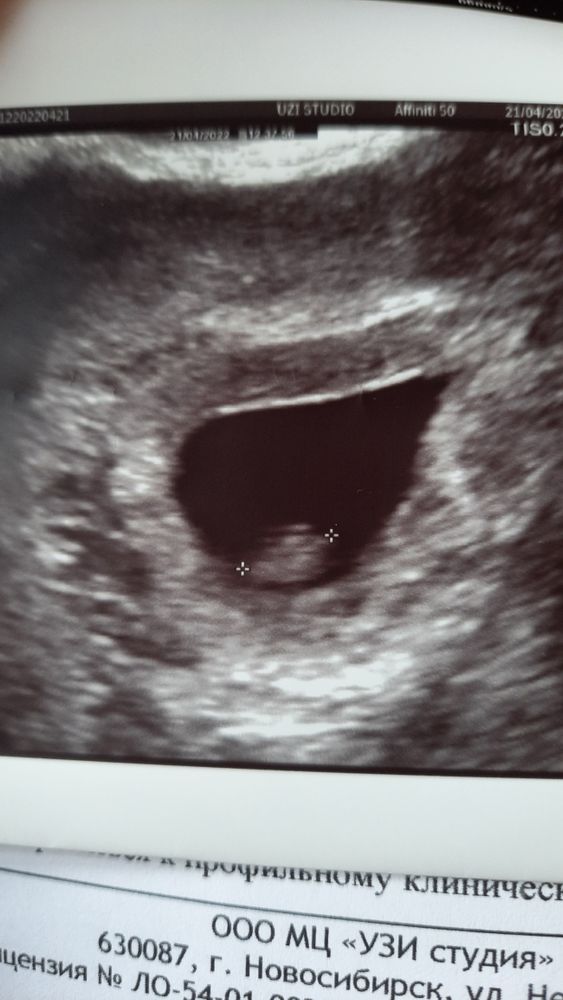

Как по мне похож на эмбрион тот шарик что слева. Вот мое узи на 5-6 неделе Изображение

Маша, у вас хорошо видно

Маша, у вас желточный мешочек слева, а не эмбрион

aleksandra, точно он, уже запамятовала 😆 как будто это было очень давно

На вашем снимке качество не очень. Вот вам для сравнения белая точечка это эмбрион, ктр тут 2,4 мм, а прозрачный кружок рядом, это жм Изображение

Наталья Иванова, ну у вас видно, а у меня не знаю даже, девочки пишут что только плодное яйцо, но мне сказали ещё эмбрион есть

Наталья Иванова, ну это да, просто интересно почему мне сказали что есть эмбрион-2,5мм😬

Жанна, да сказали ЖМ-2.2мм, но сказали ещё КТР -2.5мм

aleksandra, точно не будет 20 тысяча, но написали что КТР-2.5мм и желточный мешок-2.2мм

bravo gun, фото ужасное если честно,снизу на фото прям видно хорошо желточный,он прям ровненькие такой,края горят. Ну по УЗИ ведь в матке? Да! Желточный видно? Да, так чего переживаете то)) увидела или не увидела эмбрион, все будет)) нет поводов паниковать

aleksandra, получается у меня видно на узи желточный мешок?

Изображение Это 6 недель и 4 дня, эмбрион bravo gun, вот моё УЗИ 4 недели и 6 дней, пя 7 мм про желточный не слова,но его видно на УЗИ, фото кстати тоже фиговое Изображение

bravo gun, я, честно говоря, не вижу на вашем снимке эмбрион - только ПЯ Но я и не врач)

bravo gun, ну, какая-то полосочка есть в плодном яйце. Может, это оно?

Беременность маточная, в матке плодное яйцо. Эмбриона ещё не видно не знаю как они его намеряли , и рано ещё для эмбриона так как поздняя была О

Я тут вижу только плодное яйцо.